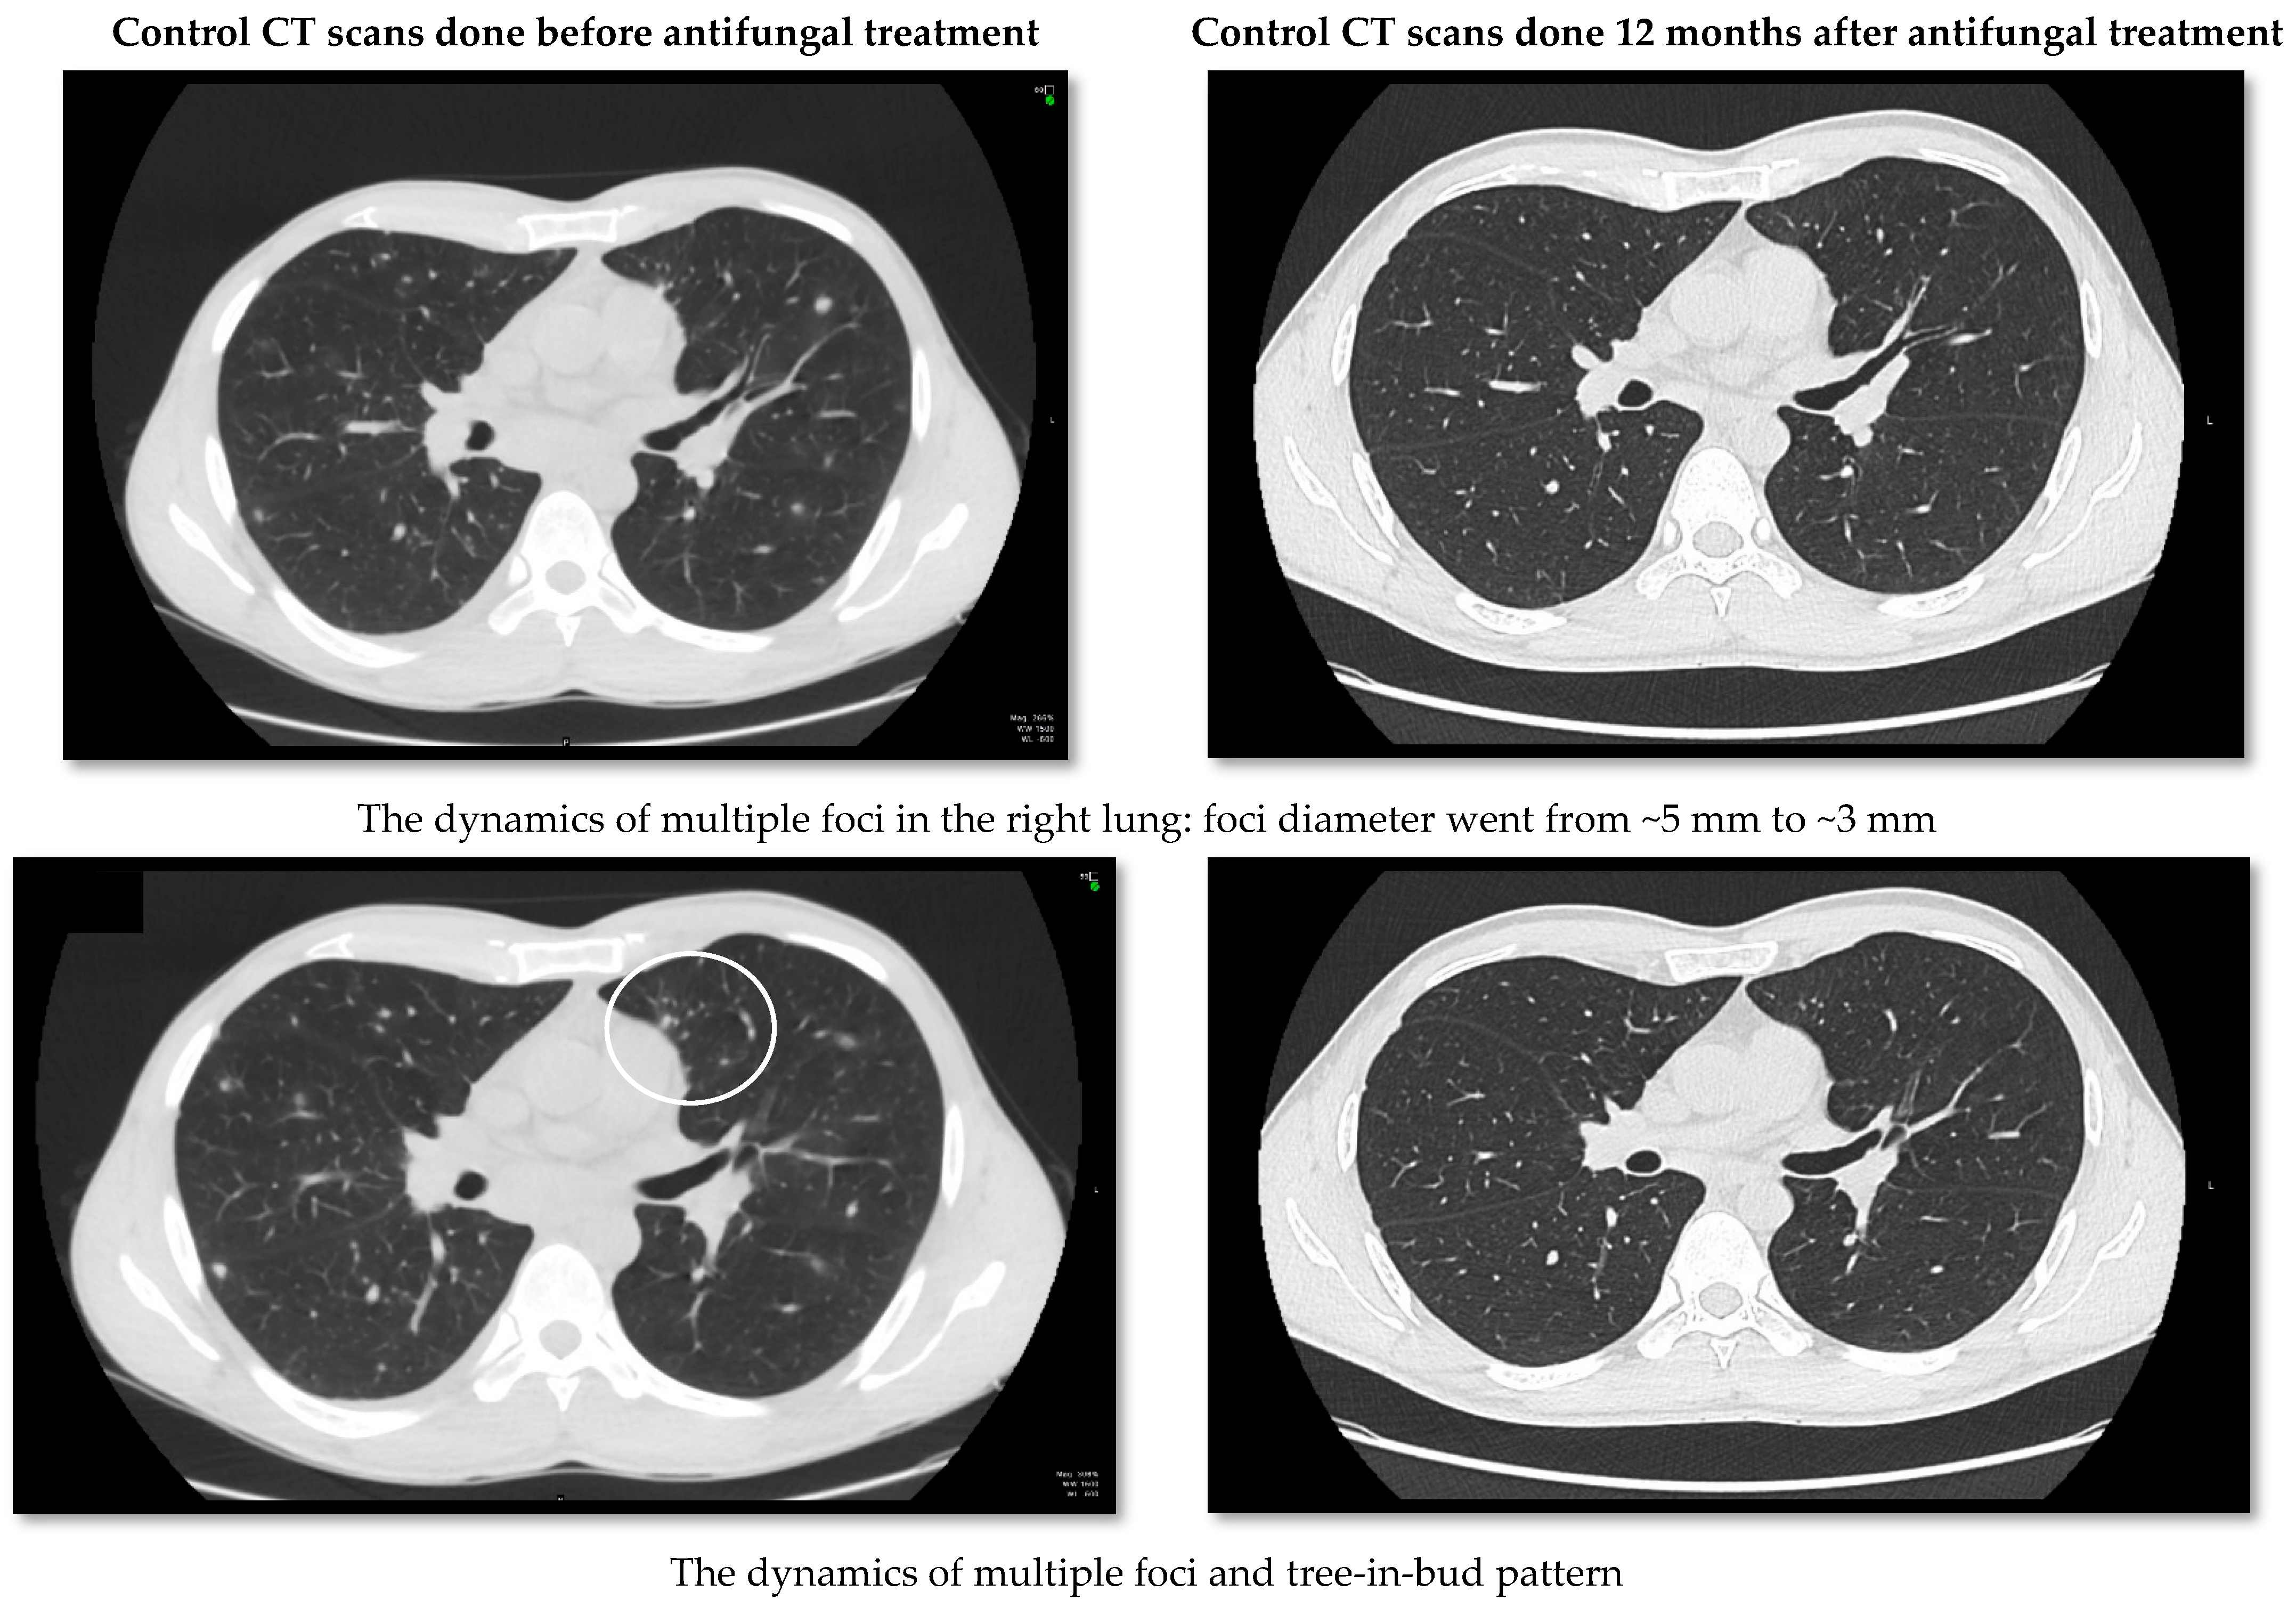

2. Case Report